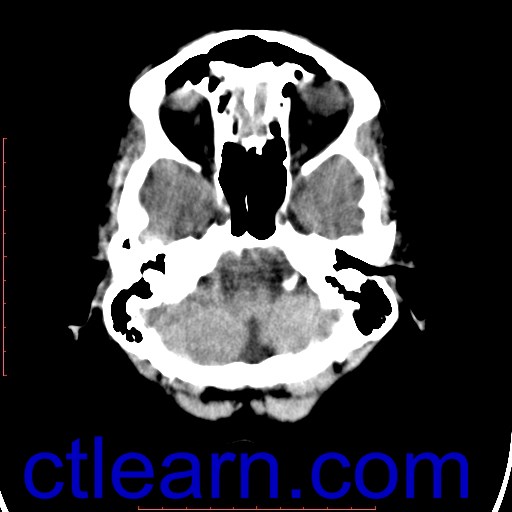

Examination: Brain. CT Scan.

Techniques: Non-Contrast Axial Scans.

Diffuse symmetrical ectasia of the supratentorial ventricular system; together with widening of the cortical sulci and sylvian fissures, as well as prominence of the basal cisterns ...

Involutional brain changes.

Normal attenuation of the cortex and white matter of both cerebral hemispheres.

No focal lesions could be detected.

No intra or extra-axial collections identified.

No mass effect; no midline shift.

Normal posterior fossa structures.

Left frontal cephalhematoma with suspected underlying small fissure fracture…for clinical correlation and follow up.